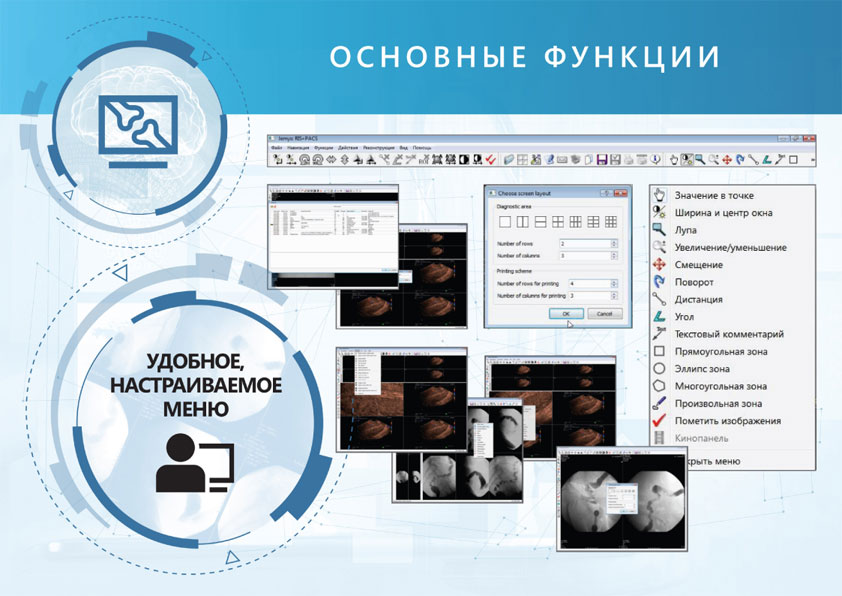

Выполняет следующие основные функции:

- Выбор строения экрана, создание любой схемы для обзорных и диагностических областей.

- Настройка панелей инструментов и контекстного меню.

- Перегруппировка изображений при помощи мыши, позволяет перетаскивать изображения из области обзорных изображений в область диагностических с использованием метода Drag and Drop.

- Перелистывание изображений при помощи пиктограмм.

- Вырезание изображений на время просмотра. С помощью данного режима помечаются изображения, которые необходимо скрыть или восстановить для просмотра/печати.

- Печать изображений. Печать изображений возможна в прямом либо обратном порядке.

- DICOM-печать: печать на DICOM-принтеры.

- Установка параметров окон (центра, яркости, ширины, контрастности).

- Измерение значения (плотности, интенсивности) пиксела (элемента изображения)

- При движений мыши по изображению, в области текстовой информации выводится информация о значении плотности в данной точке.

- Сравнение 2-х исследований: Загрузка двух и более исследований в поле обработки изображений.

- Измерение дистанции (расстояния), Калибровка изображений.

- Измерение углов.

- Выделение зон интереса (ROI) и измерение площадей. Возможно выделение прямоугольной, овальной, многоугольной и произвольной зон интереса с указанием средней плотности и площади выделенной области.

- Нанесение комментариев на изображения.

- Интерактивное увеличение/уменьшение изображений, режим смещения увеличенного изображения.

- Интерактивный поворот изображения мышью.

- Повороты на 90 градусов, отражения.

- Негатив/позитив.

- Режим динамической смены изображений (режим кино).

- Копирование изображений в буфер обмена.

- Сохранение изображений во внешних файлах. Возможно сохранение изображений в форматах JPEG, BMP, DICOM.

- Работа с протоколами исследований и шаблонами протоколов.

- Протоколы и шаблоны исследований редактируются с помощью встроенного либо внешнего текстового редактора.